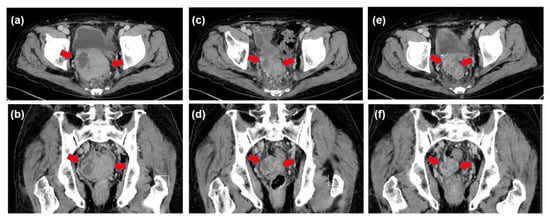

| August–October | 3D-CRT (prescribed dose for the gross tumor: 60 Gy in 30 fractions) | |

| (Decrease in the tumor size and DCP values, constipation resolved) | ||